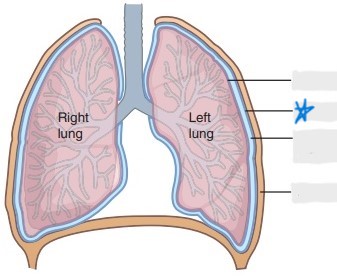

visceral pleura

parietal pleura

pleural cavity